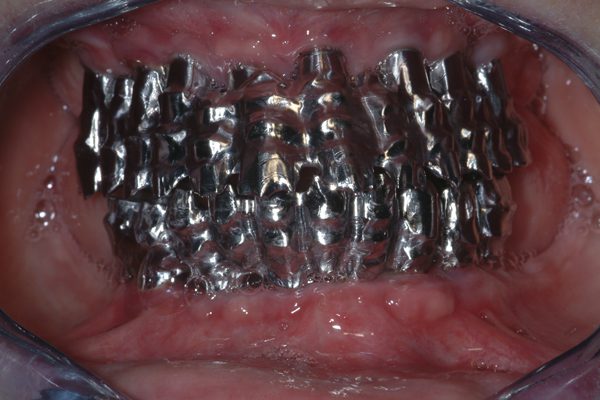

Immagine 11 Strutture protesiche metalliche con progettazione e realizzazione al CAD-CAM